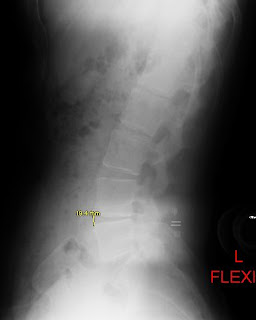

The X-Rays following my 3 month visit to the surgeon were finally sent to me and I've posted them underneath.

Here are the X-rays:-

(Hyper Flexion - X-Ray courtesy of BCH)